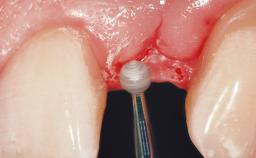

A 30-year-old female patient had lost tooth 21 and was referred to our clinic for consultation and treatment. Due to advanced apical infection, tooth 21 had been extracted two months earlier at another clinic and an acrylic-resin tooth had been bonded to the adjacent teeth. The patient desired implant treatment to avoid any damage to the adjacent natural teeth. While the patient had no history of any systemic disorder, she was a heavy smoker and exhibited medium to advanced periodontitis in the entire jaw. After the initial treatment to achieve a pocket probing depth of less than 4 mm and no bleeding on probing, a decrease in the height of the papillae mesial and distal to the extraction site and overall gingival recession were observed.

| Soft Tissue Grafting | Simultaneous |

| Soft Tissue Anatomy | Intact | Defective | |

| Soft Tissue Contour and Volume | Slightly compromised |